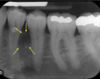

Give a differential diagnosis for the following radiographic image:

(multilocular radiolucency in right posterior mandible)

1. Odontogenic keratocyst

2. ameloblastoma

3. central giant cell granuloma